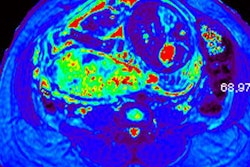

Two senior radiologists with more than five years of practical experience in abdominal MRI and two junior radiologists with less than three years of abdominal MRI experience blindly and independently reviewed MR exams for six previously defined MR features described in the literature as useful for predicting placental invasion. The features included dark intraplacental bands on T2-weighted images, a focally interrupted myometrial border, heterogeneous intraplacental signal intensity, abnormal uterine bulging, "tenting" of the bladder, and infiltration of the adjacent pelvic organs.

Overall sensitivity and specificity for placental invasion was 90.9% and 75.0%, respectively, for seniors and 81.8% and 61.8%, respectively, for juniors. The best single MR feature indicating placental invasion was T2-hypointense placental bands, followed by focally interrupted myometrial border, infiltration of pelvic organs, and tenting of the bladder.

In normal patients, the uterus presents as an inverted pear-shape organ. At MRI, the normal placenta appears as a soft-tissue structure, located along the uterine walls, with variable morphology and homogeneous, intermediate, signal intensity on T2-weighted images. In Alamo's study, T2-hypointense placental bands, a focally interrupted myometrial border, infiltration of the pelvic organs, and tenting of the bladder proved to be the best signs of predicting placental invasion.